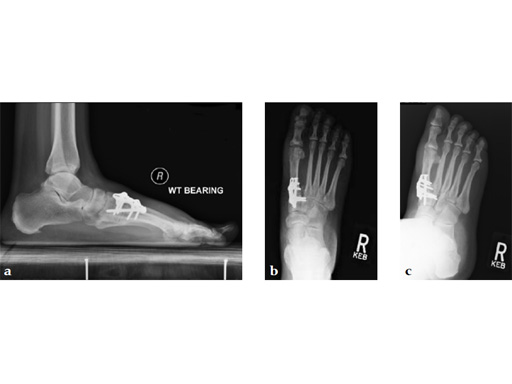

Case 2: First MTP fusion plate

A 38-year-old man presented for opinion after two attempts to fuse the big toe MTP joint. The AP view is significant for luscency at the joint line. The lateral view is notable for loosening of the hardware and malposition because of the dorsiflexion built in to the precontoured implant. Revision was planned using a 0 variable angle locking/compression hallux MTP plate.

At 10 weeks postoperatively (see Fig. 2ab) the patient had no pain with weight bearing. The lateral view demonstrates improved position of the toe using a 0angle plate.